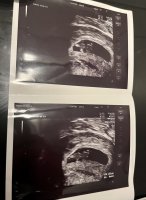

Om du tar den tidligere må du uansett ta ny etter uke 6, sa legen til meg i går. Jeg tar blodprøver på kontroll om én uke (8+6). fikk beskjed å se at det var god hjertefrekvens 155s/m og normal anatomisk utvikling

fikk beskjed å se at det var god hjertefrekvens 155s/m og normal anatomisk utvikling baby målte til 8+2 som stemmer nøyaktig med mine utregninger

baby målte til 8+2 som stemmer nøyaktig med mine utregninger